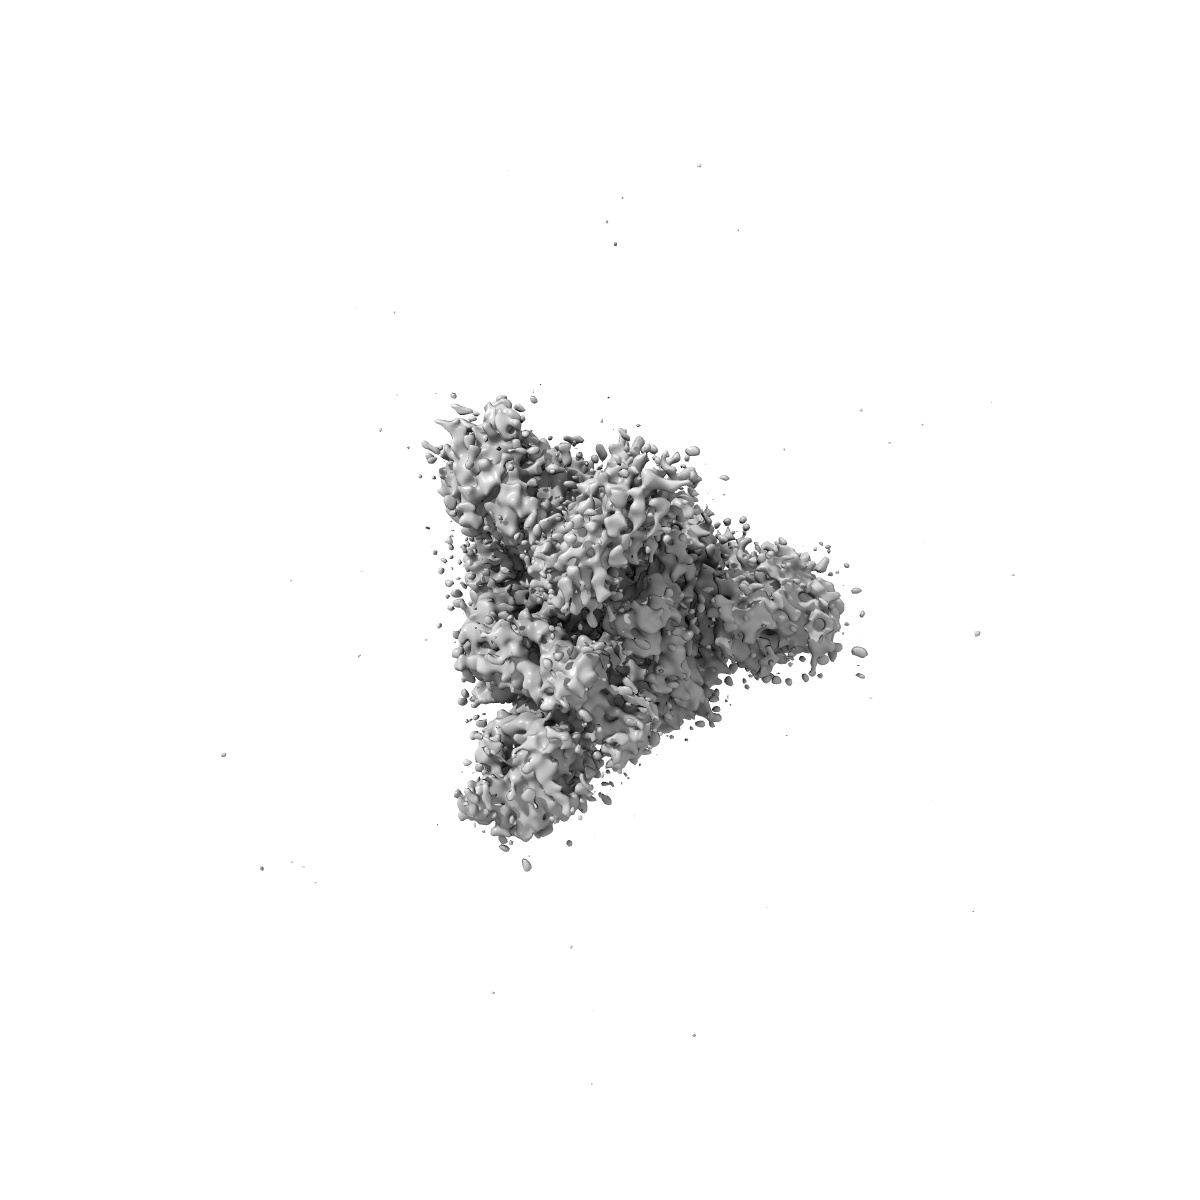

EMD-22913

Structure of the SARS-CoV-2 S 6P trimer in complex with the ACE2 protein decoy, CTC-445.2 (State 1)

Single-particle3.9 Å

Sample: Ternary complex of CTC445.2 inhibitor with SARS-CoV-2 S 6P glycoprotin